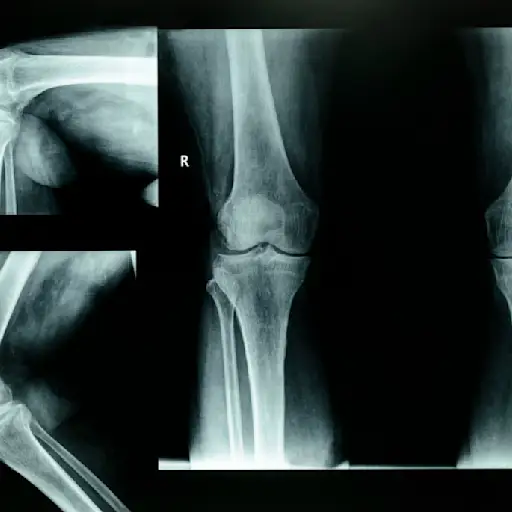

x光可能没有帮助

如果你报告关节疼痛,x光通常是医生可能使用的第一个诊断工具。然而,在疾病开始时,x光可能不会显示任何关节的变化,这困扰着你。影响软组织的早期炎症变化很可能无法用x光片检测到。只有随着病情的发展,你才能检测到骨骼结构的变化。